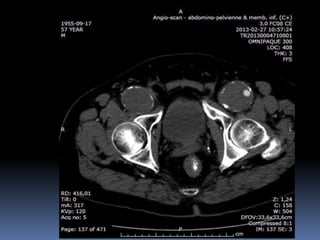

Cas #2  ♂57 ans  ATCD  Anévr. Poplité D. op ‘2000  Anévr. Poplité G. op. ‘2001  Db 2  Korsakoff  R.C. Douleurs locales à G.  Constatations…

72 59 ATCD: PABI’99 re: AIliaquebil ATCD: Db , ROH Korsakoff, MCASPAC, fempop bilat Anévr popl. Suivi Anévr fém et popl RC: référé rupture…en fait «non» mais symptomatique Quest: … Quest.:C.I. non limitante E.P.: masse puls. > 5cm ing. D non doul et autres… E.P.: masse pulsatile >5 cm ing G doul palpation, nécrose sèche extr dist un orteil non doul Pls périph N Doppler Angioscan: dimensions anévr. ? Angioscan: dimensions Anévr ?

Cas #1 72ans Cas #2 59 ans  Suivi  ATCD  PABI  Particularités  Anévrysme Fémorale profonde  Cutler-Darling type 1  Symptomatique  ATCD  Fem-pop. Bilatéraux…  Particularités  Korsakoff  Cutler-Darling type 2 thrombosés